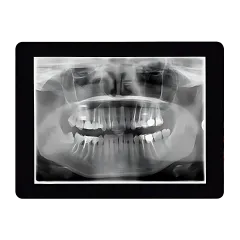

Digital X-Rays

Precision imaging is a cornerstone of great orthodontic care. At Hulme Orthodontics, we use advanced digital X-ray technology, including 3D X-rays and CBCT (Cone Beam Computed Tomography) scans, to get a complete and accurate view of your teeth, jaws, and surrounding structures.

- 3D X-Rays: These provide a full, three-dimensional view of your dental anatomy, allowing us to diagnose complex issues and plan your treatment with unmatched accuracy. From impacted teeth to jaw alignment problems, 3D X-rays help us ensure no detail is overlooked.

- CBCT Scans: For even more in-depth imaging, we use CBCT scans to assess your teeth, bone structure, airway, and sinus cavities. This technology is especially useful for patients needing surgical orthodontics or complex treatment plans, as it gives us a comprehensive view of the entire oral and facial region.

Digital X-rays are not only more precise but also safer than traditional methods, exposing you to significantly less radiation.